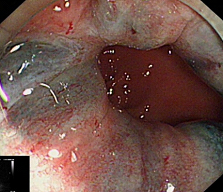

术中

术后